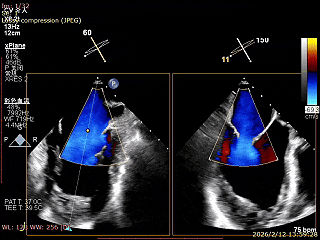

术前食道超声评估

三尖瓣关闭不全重度(4+,平均缩流颈10mm),反流口以前隔、中央为主,部分后隔,瓣叶未见明显脱垂及GAP,三尖瓣环扩张(瓣环平均径43mm),二尖瓣中-重度反流,肺动脉高压(PASP:44mmHg)。